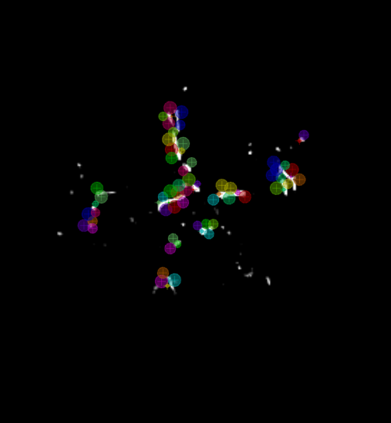

During the diagnosis of ischemic strokes, the Circle of Willis and its surrounding vessels are the arteries of interest. Their visualization in case of an acute stroke is often enabled by Computed Tomography Angiography (CTA). Still, the identification and analysis of the cerebral arteries remain time consuming in such scans due to a large number of peripheral vessels which may disturb the visual impression. In previous work we proposed VirtualDSA++, an algorithm designed to segment and label the cerebrovascular tree on CTA scans. Especially with stroke patients, labeling is a delicate procedure, as in the worst case whole hemispheres may not be present due to impeded perfusion. Hence, we extended the labeling mechanism for the cerebral arteries to identify occluded vessels. In the work at hand, we place the algorithm in a clinical context by evaluating the labeling and occlusion detection on stroke patients, where we have achieved labeling sensitivities comparable to other works between 92\,\% and 95\,\%. To the best of our knowledge, ours is the first work to address labeling and occlusion detection at once, whereby a sensitivity of 67\,\% and a specificity of 81\,\% were obtained for the latter. VirtualDSA++ also automatically segments and models the intracranial system, which we further used in a deep learning driven follow up work. We present the generic concept of iterative systematic search for pathways on all nodes of said model, which enables new interactive features. Exemplary, we derive in detail, firstly, the interactive planning of vascular interventions like the mechanical thrombectomy and secondly, the interactive suppression of vessel structures that are not of interest in diagnosing strokes (like veins). We discuss both features as well as further possibilities emerging from the proposed concept.